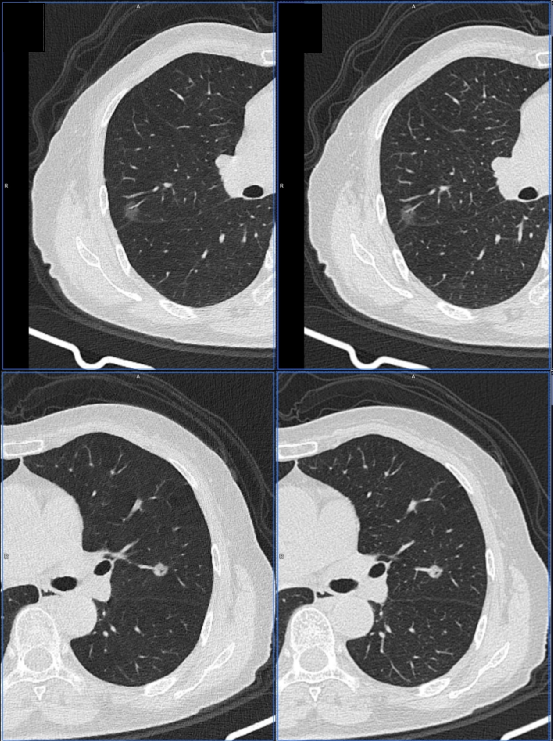

四个不同软件对磨玻璃结节的分割和体积分析。计算的结节体积为A、2019 mm3,B、2059 mm3,C、1949 mm3,D、1528 mm3,导致测量之间的最大差值为531 mm3。